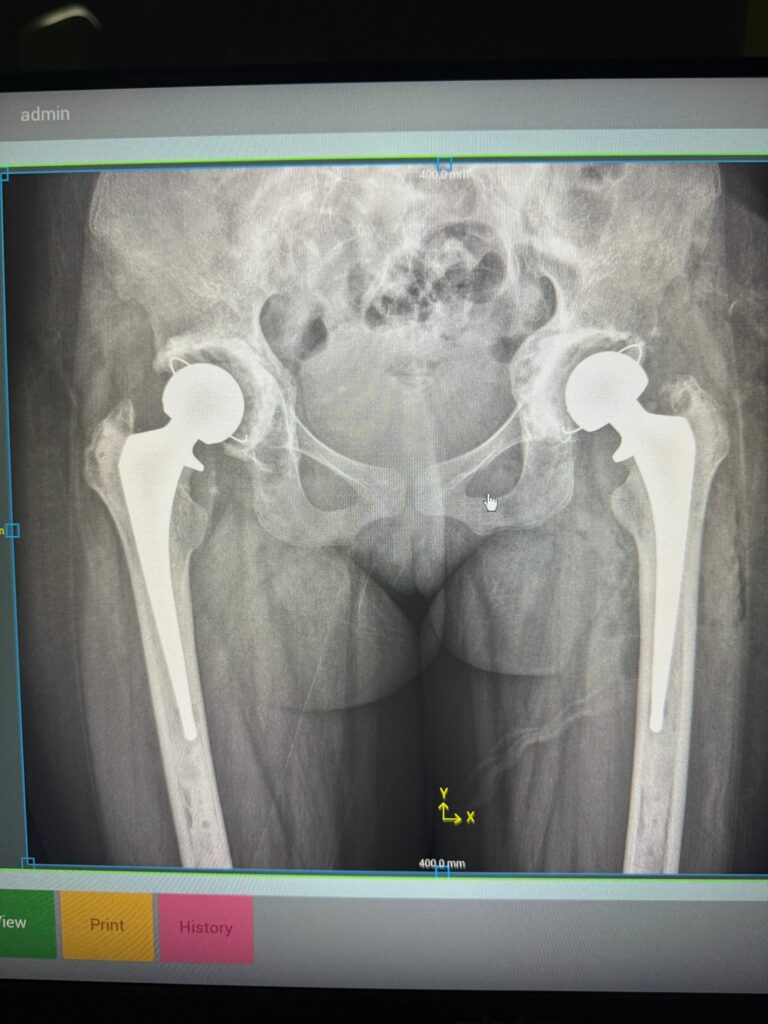

La duodécima campaña quirúrgica dedicada a la implantación de prótesis de cadera en pacientes con anemia drepanocítica se desarrolló con excelentes resultados clínicos y organizativos.

Durante la misión se operó con éxito a 11 pacientes, todos ellos con cuadros complejos derivados de la enfermedad, pero con una evolución postoperatoria favorable.